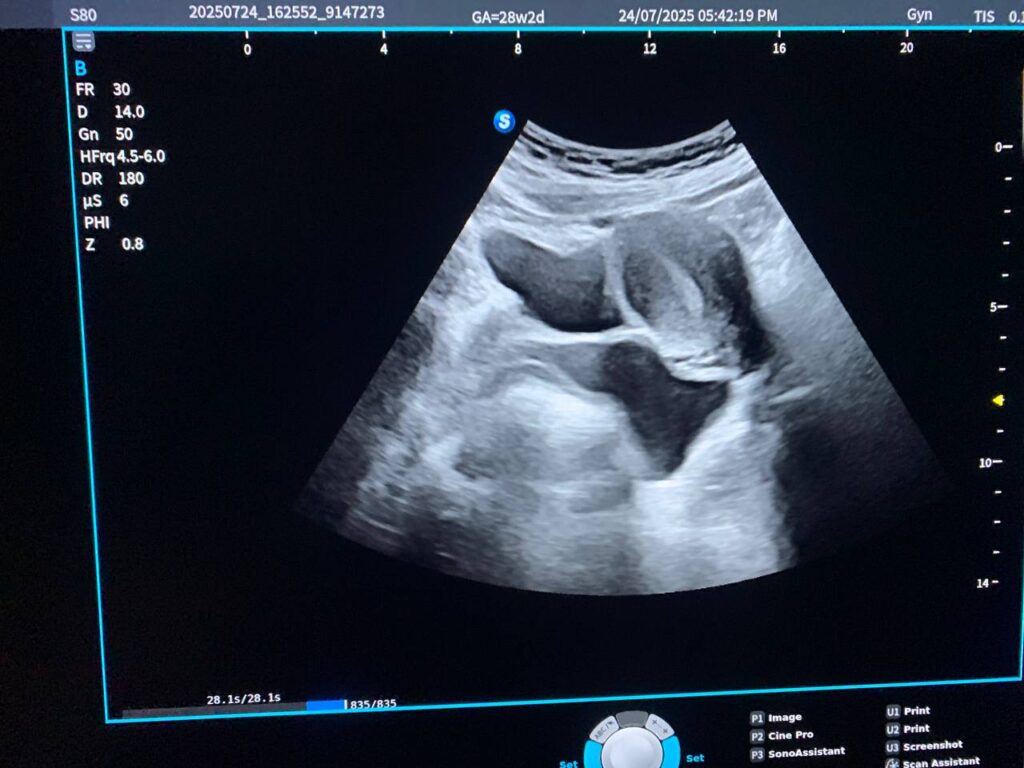

Presence of tortuous cystic mass size about 52x39mm, on the left sided posterior uterus & left vaginal canal , its located of the sacral region , Tarlov cyst cannot be excluded